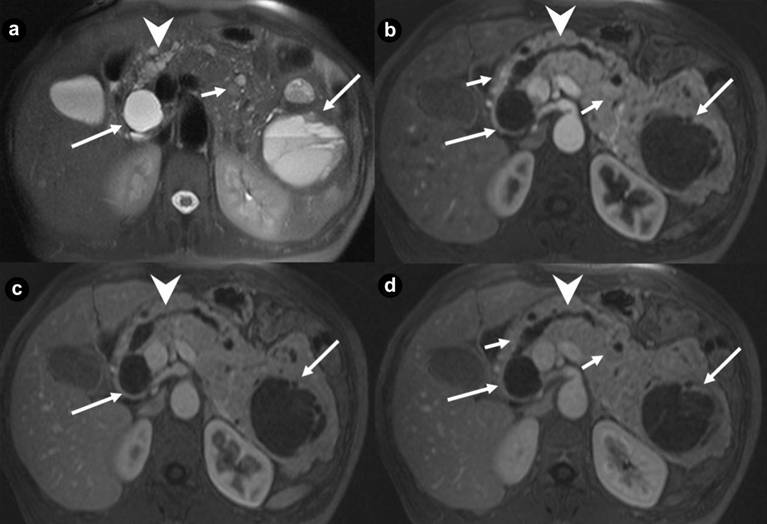

Figure 2. Pancreatic non functioning neuroendocrine tumors. Two cases suffering from VHL syndrome: a 39-year-old man (a. b.), and a 37-year-old man (c. d.). Coronal (a. c.) T2-weighted MR images; axial (b. d.) 3D volumetric gradient-echo T1-weighted fat suppressed images after intravenous contrast medium administration during arterial pancreatic phase of contrastographic dynamic study. In pancreatic head, a small, nodular solid lesion with maximum diameter of 12 mm (a. b. arrow), hyperintense on T2-weighted MR images, with homogeneous enhancement after intravenous contrast medium administration during arterial pancreatic phase is present. Main pancreatic duct is normal and common bile duct is not dilated. Small complex cystic mass in the right kidney without enhancement after intravenous contrast medium administration (b.) is present (short arrow). In pancreatic body-tail a solid, round mass with maximum diameter of 23 mm (c. d. arrow), heterogeneously hyperintense on T2-weighted MR images, with homogeneous enhancement after intravenous contrast medium administration during arterial pancreatic phase, is present. Artifacts are recognizable in the site of right adrenal gland (arrowhead), due to the presence of metallic staples of previous adrenalectomy for pheochromocytoma. |

Figure 3. Pancreatic non functioning neuroendocrine tumor and pancreatic serous cystadenoma in the same patient: asymptomatic 24-year-old man. Axial (a. b.) T2-weighted MR images, axial 3D volumetric gradient-echo T1-weighted fat suppressed images after intravenous contrast medium administration during arterial pancreatic (c. d.) and portal venous (e. f.) phases of contrastographic dynamic study. In pancreatic head a solid mass (a. arrow), heterogeneously hyperintense on T2-weighted MR images (a.) with homogeneous enhancement after intravenous contrast medium administration during arterial pancreatic phase of contrastographic dynamic study (c.), without wash-out in portal venous phase (e.) is present. In pancreatic head a cystic parenchymal lesion (short arrow), more hyperintense than solid mass, with fluid signal intensity on T2-weighted MR images (b.), without enhancement after intravenous contrast medium administration during arterial pancreatic (d.), and portal venous phases (f.), is visible. Inside the cystic lesion a septa is recognizable. Pancreaticoduodenectomy with Whipple procedure was performed. Histological specimen showed the presence of pancreatic macrocystic serous cystadenoma and non functioning neuroendocrine tumor of pancreatic head. |

Thirty-four pancreatic lesions were found in the 23 patients. In qualitative analysis, the MR imaging findings were: 6 (26.1%) unilocular fluid cystic lesions (Figure 1abc): 3 (13.0%) in pancreatic head, 3 (13.0%) in pancreatic body-tail; 11 (47.8%) serous micro- or micro/macro-cystic cystadenomas (Figures 1def, 4, and 5): 1 (4.3%) in pancreatic head, 2 (8.7%) in pancreatic body-tail (Figure 1), 8 (34.8%) diffuse (Figures 4 and 5); 8 (34.8%) neuroendocrine solid tumors: all of them non-functioning NET and hypervascular during arterial pancreatic phase of contrastographic dynamic study (Figures 2, 3, 4, and 5), 4 (17.4%) at pancreatic head (Figures 2ab; 3ace, and 4), 4 (17.4%) at pancreatic body-tail (Figures 2cd and 5); 1 (4.3%) cystic non-functioning NET, diffuse in all pancreatic gland (Figure 6); in 4 (17.4%) cases association of non-functioning NET and pancreatic cystic lesions (3 cases of association of non-functioning NET and serous cystadenoma (13.0%); 1 case of association of non-functioning NET and pancreatic simple cystic lesion (4.3%)) were present (Figures 4 and 5). Vascular invasion was not detected in any patients.

At MR images [15, 24, 25, 26, 28, 29, 30, 33] these tumors are oval or round lesions, with well-demarcated margins, hypointense on the T1-weighted images, and show higher signal intensity than normal pancreatic parenchyma on T2-weighted images, but they have no so high signal intensity as cysts (Figures 2ac, 3a, 4bc, and 5bc).

They show intense and early enhancement after gadolinium-chelates injection during MR dynamic study, resulting hyperintense masses at enhanced pancreatic phase of MR study (Figures 2bd, 3c, 4e, and 5d), with a reduced or moderate reduced or non reduced signal intensity in successive venous and delayed phases of dynamic study because of wash-out, or low wash-out, or no wash-out of gadolinium contrast medium, respectively.

The smaller tumors enhanced homogeneously, while the larger tumors tend to enhance heterogeneously after contrast medium administration during the pancreatic arterial and portal venous phases on MR images. The vascular heterogeneity may be a sign of malignancy, since malignant lesions are often heterogeneous in vascular structure, perfusion, and vascular permeability [24, 25, 26, 27]. As tumors grow, the central portions become less vascularized, so necrotic areas and calcifications may compare [24, 25, 26].

Differently to literature, in our series non functioning NETs had not a preferential site in pancreatic gland, resulting localized in 17.4% of cases in the pancreatic head (Figures 2ab, 3, and 4) and 17.4% in pancreatic body-tail (Figures 2cd and 5).